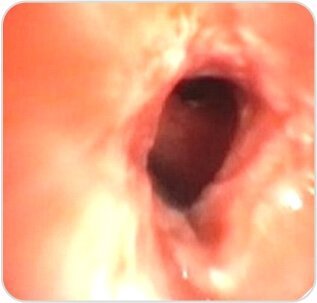

Fiber Optic Bronchoscopy revealed – Multi Level Fibrostenosis of the left main bronchus with complete obstruction of the distal LMB 2.7 cms from the primary carina and 1 cm above the second carina on the left side was noted.

Pre – Procedure

Step 1